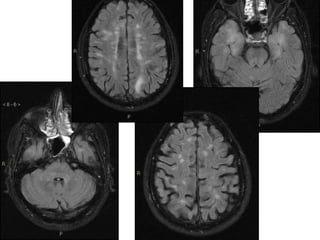

• Brain

Although traditionally NMO was thought to have

normal intracranial appearance it is increasingly evident

that in the majority of patients asymptomatic

abnormalities are present. These can be divided into

four categories:

• Lesions which mirror distribution of aquaporin 4 in the

brain, which is particularly found in the periependymal

brain adjacent to the ventricles:

– periventricular (hemispheric) confluent white matter

involvement (unlike MS there are usually no Dawson's fingers)

– periaqueductal grey matter

– hypothalamus/medial thalamus

– dorsal pons/medulla

– corpus callosum

• multiple callosal lesions with heterogeneous signal leading to

a marbled pattern

• splenium may be diffusely involved and expanded

Typical periependymal lesions following the known distribution of AQP4. A and B, FLAIR MR

imaging shows hypothalamic and medullary lesions in symptomatic AQP4-positive NMO

spectrum disorder C and D, FLAIR MR imaging shows midbrain tegmentum lesions during

second attack

• Deep (or less frequently subcortical) punctate

white matter lesions (which may appear

similar to those seen in multiple sclerosis).

• Corticospinal tract involvement by extensive

longitudinal lesions.

• Larger "spilled ink pattern" of hemispheric

white matter lesions which often vanish with

steroid administration.

• Unlike MS, NMO does not appear to involve

the cortex

• Brain Although traditionallyNMO was thought to have normal intracranial appearance it is increasingly evident that in the majority of patients asymptomatic abnormalities are present. These can be divided into four categories: • Lesions which mirror distribution of aquaporin 4 in the brain, which is particularly found in the periependymal brain adjacent to the ventricles: – periventricular (hemispheric) confluent white matter involvement (unlike MS there are usually no Dawson's fingers) – periaqueductal grey matter – hypothalamus/medial thalamus – dorsal pons/medulla – corpus callosum • multiple callosal lesions with heterogeneous signal leading to a marbled pattern • splenium may be diffusely involved and expanded

Typical periependymal lesionsfollowing the known distribution of AQP4. A and B, FLAIR MR imaging shows hypothalamic and medullary lesions in symptomatic AQP4-positive NMO spectrum disorder C and D, FLAIR MR imaging shows midbrain tegmentum lesions during second attack